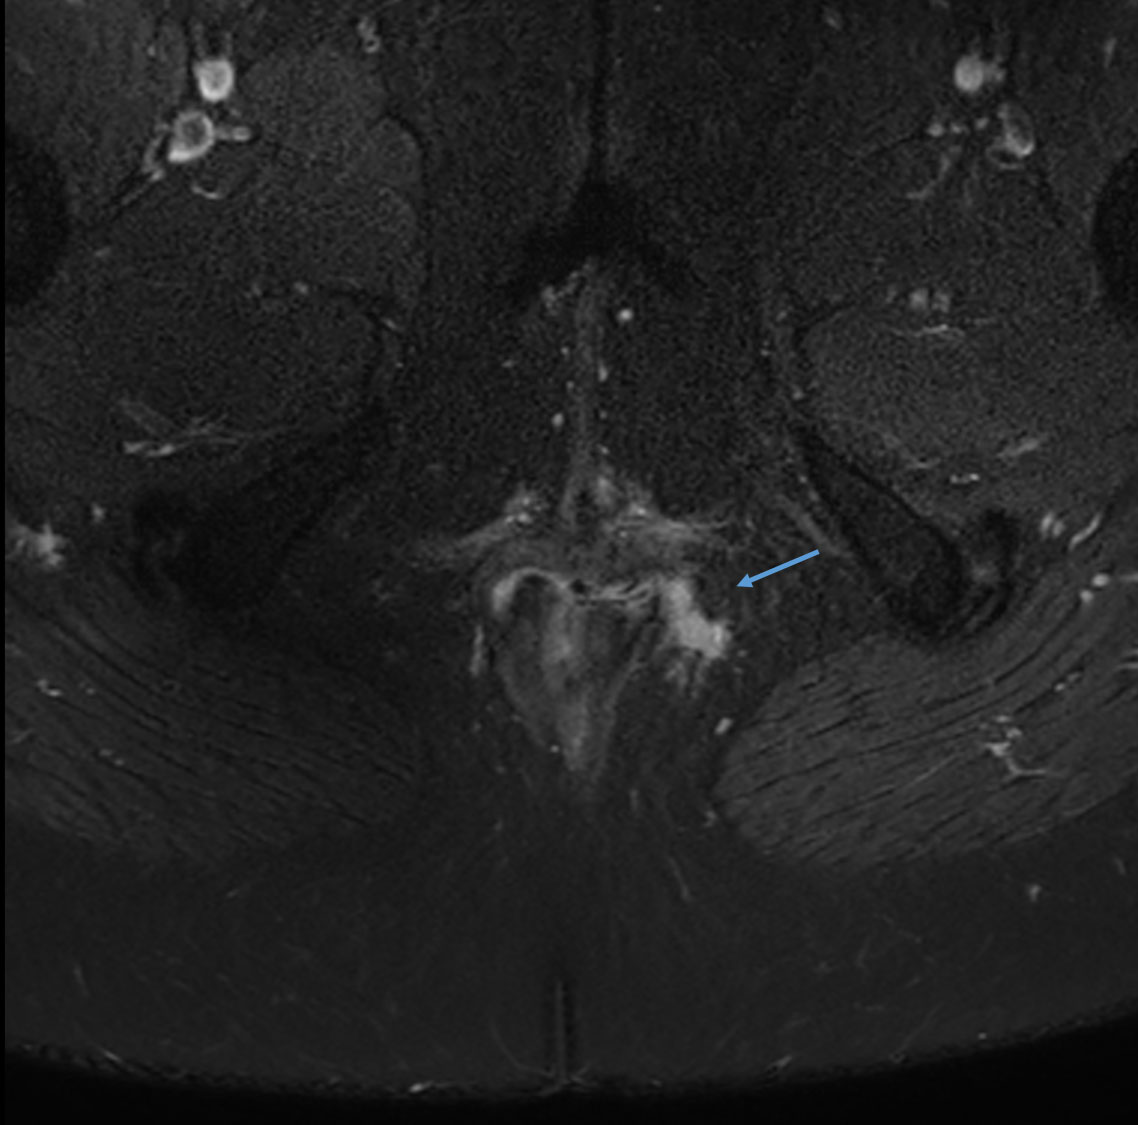

Axial T2w SPAIR

Axial T1w SPIR with gado